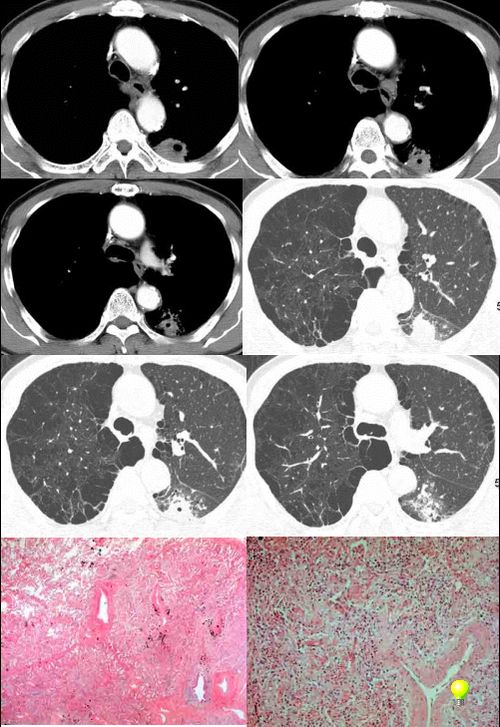

⑧患者,男,48岁,于2001年因“反复声嘶9个月”在外院确诊为喉鳞状上皮癌,行手术切除。10天前患者无明显诱因出现左侧背部疼痛,进行性加重,患者无咳嗽、咳痰、发热。

实验室检查:ce125:128uml ly:0. 6x109/l wbc:10.1x109/l ne:8.3x109/l

左上肺炎性假瘤:

细支气管上皮增生、纤维母细胞增生及纤维化,间质有炎细胞浸润及淋巴滤泡形成,边缘有坏死组织。

⑨男,52岁,痰中带血两天。无明显发热,化验室检查正常。

⑩女,58岁。无不适,体检发现胸部肿物,行ct检查。